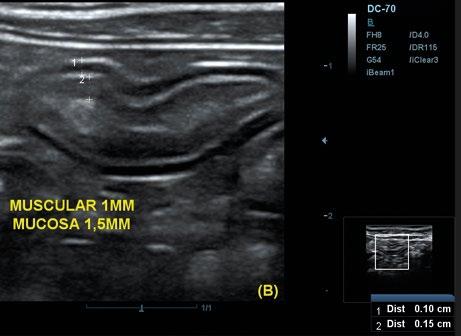

Utilidad clínica de la ecografía pulmonar y cardiaca en urgencias